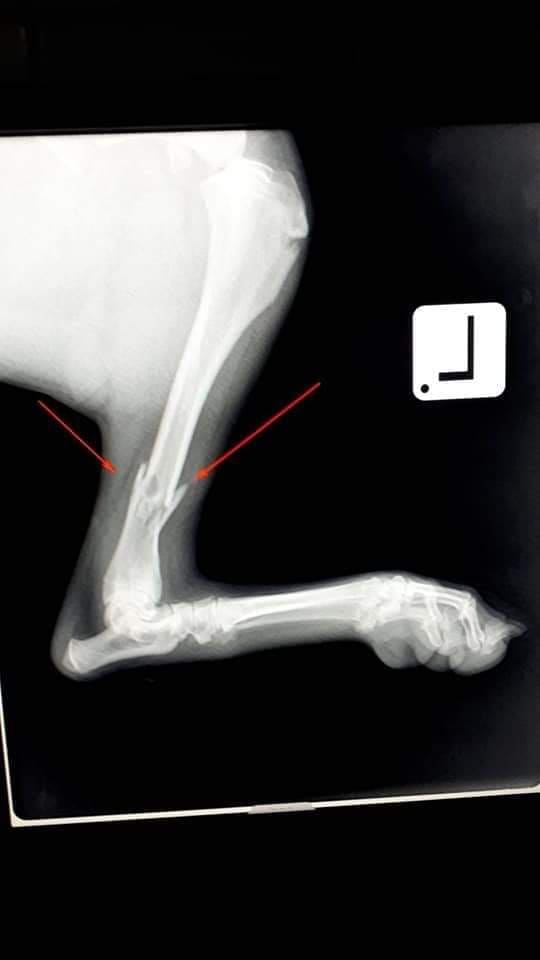

Stigli su i RTG snimci  na osnovu kojih su dijagnosticirane frakture obje butne kosti kao i fraktura tibie.

Ortopedski zahvat jedne noge je predviđen za sutra u saradnji sa Veterinarskom stanicom PET DOC 4U Lukavac, dok će fraktura na drugoj nozi biti sanirana tri dana nakon prvog zahvata.